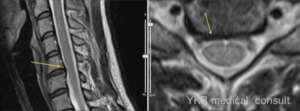

本件では、下図のとおり、第5頚椎と第6頚椎に椎間板膨隆が認められる。

この点、右上肢の疼痛及び右手指のしびれ等の神経症状は本件事故以降に一気に発生しており、当該神経症状と上記画像所見との整合性も認められる。